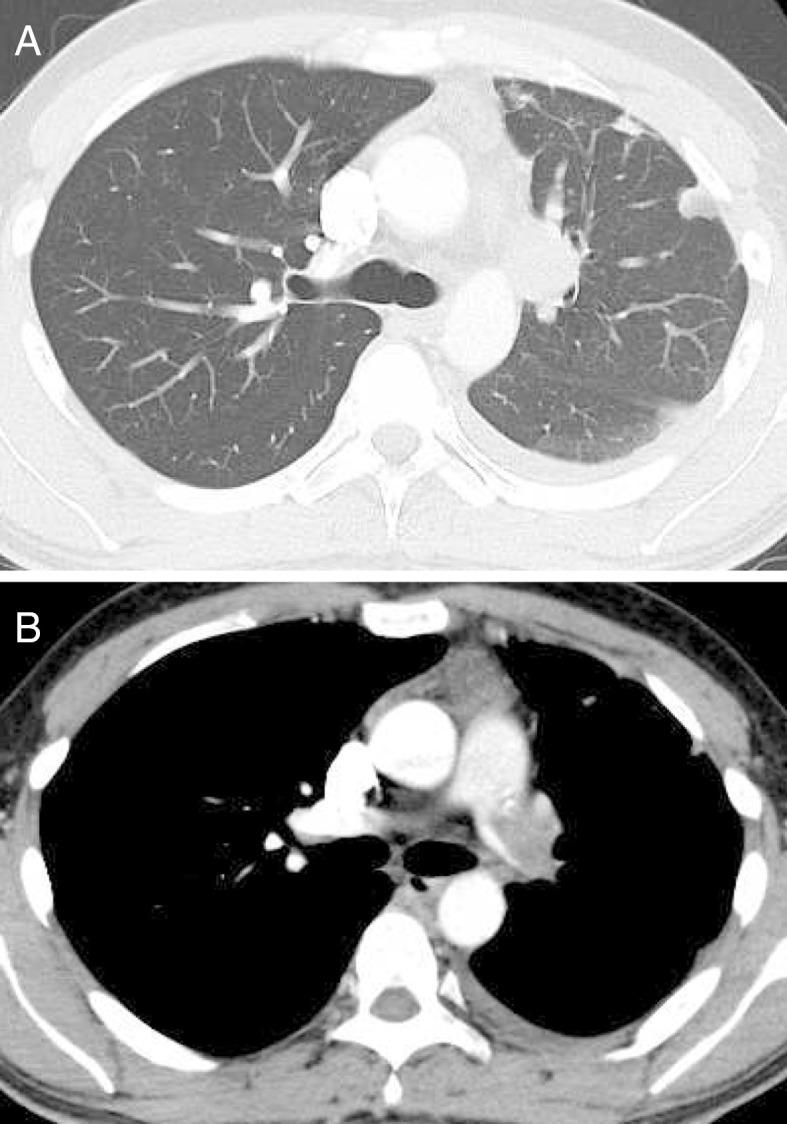

The Notable Appearance of Pulmonary Artery Intimal Sarcoma on Positron Emission Tomography (PET)/CT.

https://cdn.ncbi.nlm.nih.gov/pmc/blobs/5cb3/5709647/8828236cc703/1349-7235-56-2953-g001.jpg